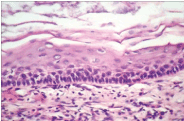

Figure 2. Odotogenic Keratocyst- with compressed stratified squamous lining.